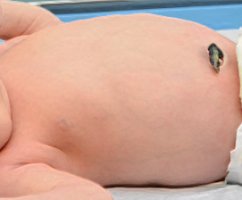

Новорождённые

Смотреть все

Уход за новорождённым

Смотреть все

Появление в доме новорождённого младенца, это всегда огромная радость для его родителей. Новоиспечённые мама с ...